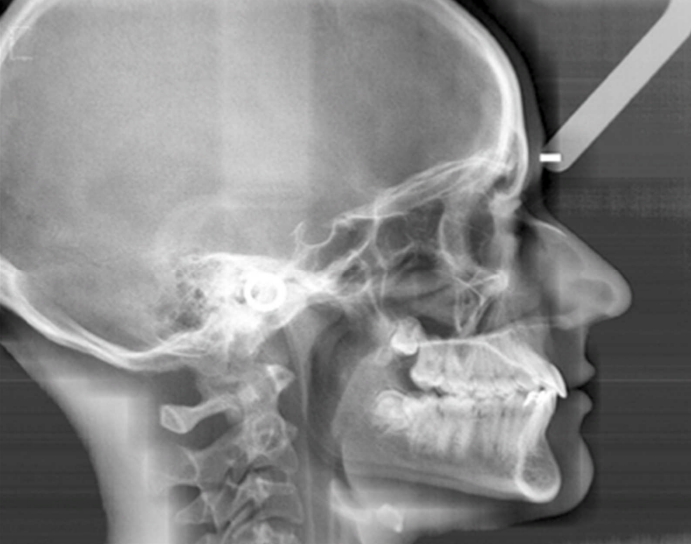

Téléradiographie de Profil (Norma Lateralis)

La téléradiographie de profil constitue l’examen radiographique de référence en orthodontie. Elle fait partie des examens systématiques et permet une analyse exhaustive des structures cranio-faciales.

Positionnement du patient : La tête est immobilisée dans une position rigoureusement standardisée grâce à un céphalostat. Cette immobilisation garantit la reproductibilité des clichés, essentielle pour le suivi longitudinal.

Principes Techniques de la Téléradiographie

Conditions de Réalisation Standardisées

La distance foyer-objet importante (initialement supérieure à 4 mètres) minimise la déformation de l’image et permet des mesures céphalométriques fiables.